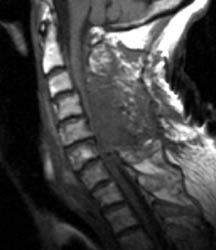

75 y.o. female with about a two-year history of continued gait abnormalities

and decreased dexterity. On examination her strength was normal, however, she

had bilateral Hoffmann signs as well as bilateral Babinski signs. Her strength

was 5/5 but her gait was ataxic. Magnetic resonance imaging showed severe

stenosis at C3, C5 and C6 levels. She underwent C3-C6 laminectomies.

Immediately post-operatively she did well, however, within 36 hours of the

operation, she slipped and fell due to spilled milk on the floor . After that

injury, the patient was neurologically intact. However, on postoperative day #2

for morning rounds, the patient was noted to be confused and weakened on the

left side, both arm and leg, leg more than the arm. An immediate CAT scan of the

brain and cervical spine was obtained. Immediate MRI was also obtained.

Non-enhanced sagittal T1 (A), sagittal T2 (B) and axial T1

images demonstrate a large fluid collection,

predominantly low signal on T1, bright on T2 with a few areas of T1 hyperintesity

mixed within. These constellation of findings are consistent with a

post-operative epidural hematoma with blood products of various ages. There is

severe severe spinal canal stenosis at C3-4, and very severe spinal canal

stenosis at C4-5 and C5-6. The cord is markedly flattened in the

anterior-posterior dimension, to approximately 2-3 mm secondary to mass effect

from this fluid collection. There is abnormal T2 weighted hyperintensity within

the substance of the cord at the C5-6 and C6-7 levels, consistent with some

edema.